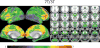

Whole-brain functional magnetic resonance imaging (fMRI), in conjunction with multiband acceleration, has played an important role in mapping the functional connectivity throughout the entire brain with both high temporal and spatial resolution. Ultrahigh magnetic field strengths (7T and above) allow functional imaging with even higher functional contrast-to-noise ratios for improved spatial resolution and specificity compared to traditional field strengths (1.5T and 3T). High-resolution 7T fMRI, however, has primarily been constrained to smaller brain regions given the amount of time it takes to acquire the number of slices necessary for high resolution whole brain imaging. Here we evaluate a range of whole-brain high-resolution resting state fMRI protocols (0.9, 1.25, 1.5, 1.6 and 2mm isotropic voxels) at 7T, obtained with both in-plane and slice acceleration parallel imaging techniques to maintain the temporal resolution and brain coverage typically acquired at 3T. Using the processing pipeline developed by the Human Connectome Project, we demonstrate that high resolution images acquired at 7T provide increased functional contrast to noise ratios with significantly less partial volume effects and more distinct spatial features, potentially allowing for robust individual subject parcellations and descriptions of fine-scaled patterns, such as visuotopic organization.